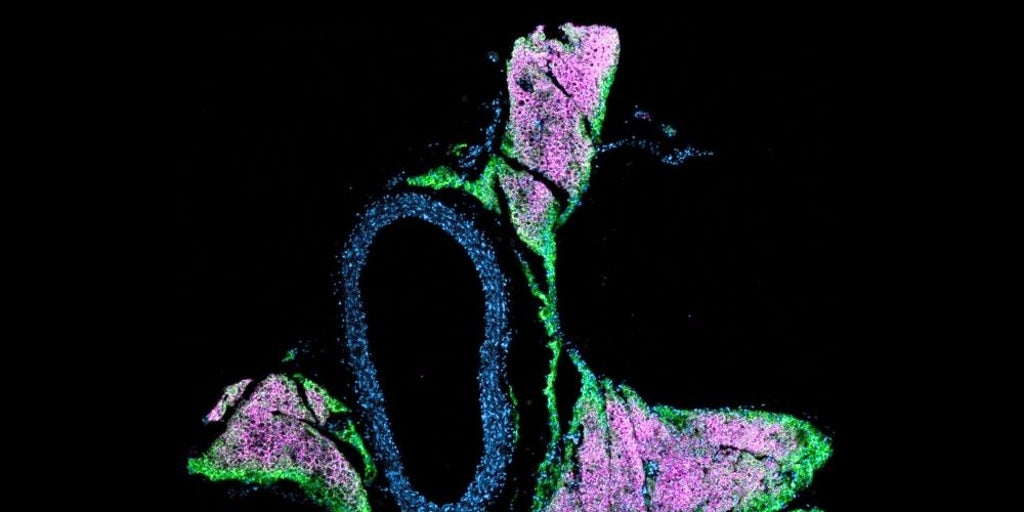

Un nuevo estudio demuestra cómo la grasa parda o beige termogénica, un tipo de tejido adiposo distinto de la grasa blanca que ayuda al cuerpo a quemar energía, influye directamente en la regulación de la presión arterial....